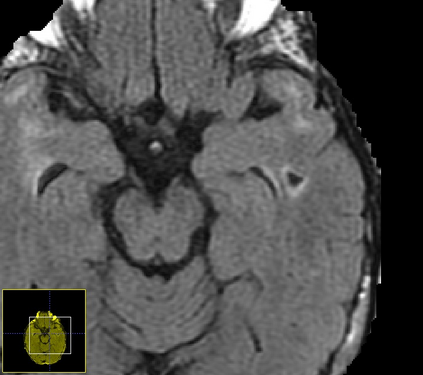

Imaging markers of cerebral small vessel disease provide valuable information on brain health, but their manual assessment is time-consuming and hampered by substantial intra- and interrater variability. Automated rating may benefit biomedical research, as well as clinical assessment, but diagnostic reliability of existing algorithms is unknown. Here, we present the results of the \textit{VAscular Lesions DetectiOn and Segmentation} (\textit{Where is VALDO?}) challenge that was run as a satellite event at the international conference on Medical Image Computing and Computer Aided Intervention (MICCAI) 2021. This challenge aimed to promote the development of methods for automated detection and segmentation of small and sparse imaging markers of cerebral small vessel disease, namely enlarged perivascular spaces (EPVS) (Task 1), cerebral microbleeds (Task 2) and lacunes of presumed vascular origin (Task 3) while leveraging weak and noisy labels. Overall, 12 teams participated in the challenge proposing solutions for one or more tasks (4 for Task 1 - EPVS, 9 for Task 2 - Microbleeds and 6 for Task 3 - Lacunes). Multi-cohort data was used in both training and evaluation. Results showed a large variability in performance both across teams and across tasks, with promising results notably for Task 1 - EPVS and Task 2 - Microbleeds and not practically useful results yet for Task 3 - Lacunes. It also highlighted the performance inconsistency across cases that may deter use at an individual level, while still proving useful at a population level.